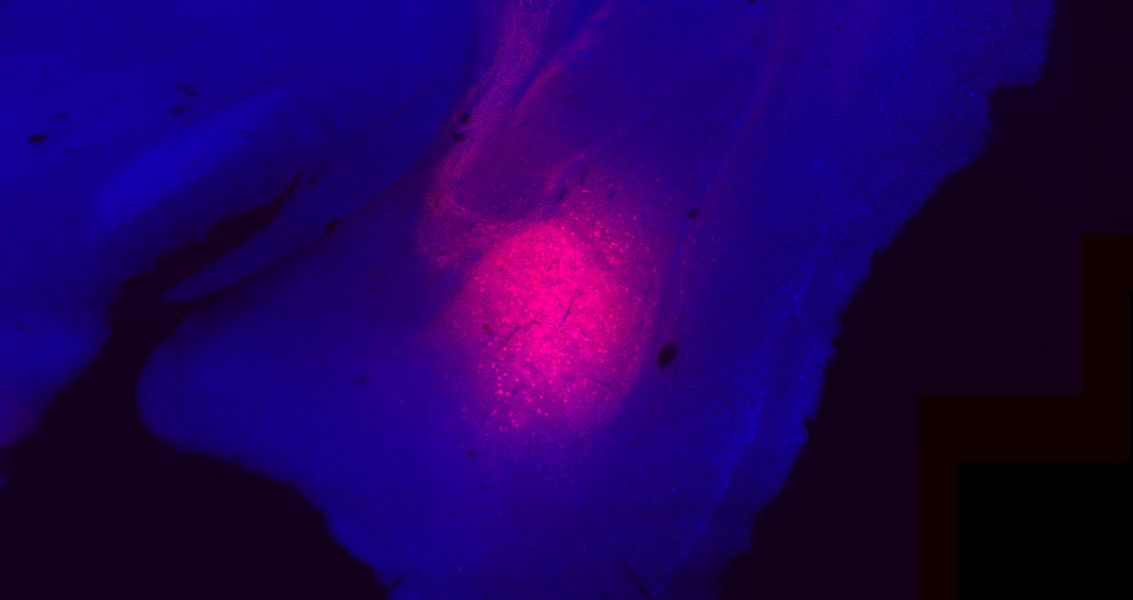

Az amygdala kapcsolatrendszere

Az amygdala - az egyik legintenzívebben kutatott agyterület –, egy rendkívül összetett, agykérgi és kéreg-alatti elemekből álló hálózat központi eleme. Fontos szerepet játszik az érzelmek szabályozásában és a tanulásban, de olyan pszichiátriai megbetegedésekkel is kapcsolatba hozták, mint a szorongás vagy a poszt-traumás stressz.

Laborunkban ezért azon dolgozunk, hogy jobban megértsük az amygdala belső- és külső kapcsolatrendszerét, amihez különböző neuroanatómiai és elektrofiziológiai módszereket használunk fel. Reményeink szerint kutatásaink hosszú távon hozzájárulnak ahhoz, hogy az amygdalával kapcsolatos, ma még megválaszolatlan kérdések megoldódjanak.

Az amygdala szépségei